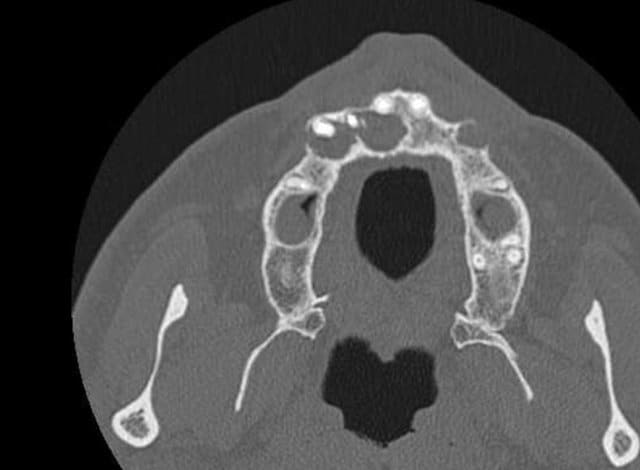

Voilà j'ai mieux que la gutta (pas de fistule visible en ce moment de toute façon )

Un scan. Voici quelques extraits.

Donc on extrait tout ce qui reste devant, on est d'accord ?

13 parait fenestrée de vestibulaire en palatin

donc ROG à ce niveau indispensable non ?

Un scan (ou cone beam) te permettra de visualiser avec précision l'étendue de la lésion.. peut être de mettre en évidence une fenestration de 13 (indication de chir endo).